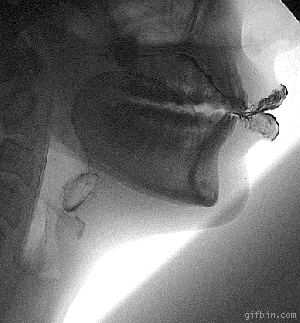

입 X-Ray